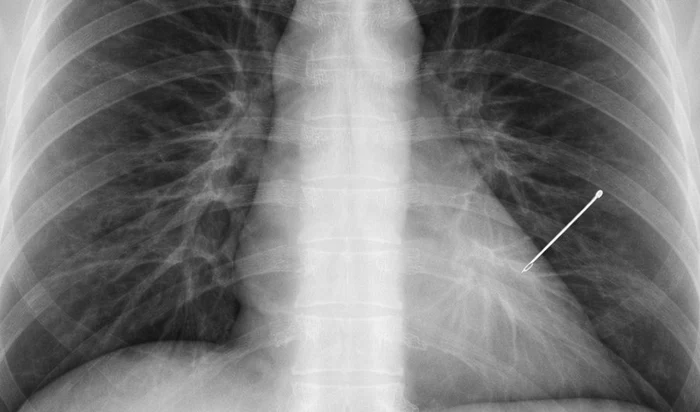

Un caz medical neobișnuit a fost descoperit întâmplător la o femeie de 55 de ani, în timpul unui control de rutină: o radiografie a arătat prezența unui ac de cusut în plămânul stâng, care ar fi rămas în organism, timp de aproape 30 de ani.

„Radiografia care m-a lăsat fără cuvinte după 20 de ani de experiență. În radiologie vezi de toate. După 20 de ani, crezi că nimic nu te mai poate surprinde. Și totuși. O pacientă de ~55 de ani vine pentru o radiografie pulmonară de rutină. Control periodic, nimic special. Pun radiografia pe ecran. Și îngheț. În plămânul stâng, clar vizibil, un ac de cusut”, a relatat medical.

Radiologul spune că acul ar fi rămas în organism fără să provoace probleme majore: „30 de ani. Acul migrase și stătea cuminte în plămân fără să facă probleme.”